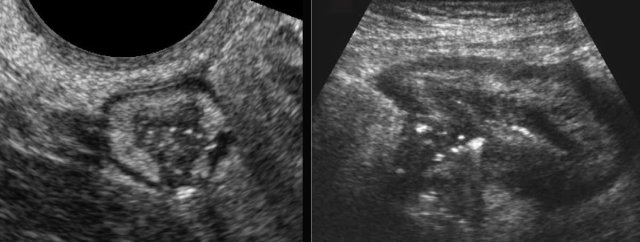

Two patients with Crohn’s abscesses close to the ileum.

Note that abscesses in Crohn’s disease are often small and collapsed.

The explanation for this phenomenon  is that these abscesses usually have an open connection to the ileal lumen, allowing pus to immediately evacuate to the bowel lumen when pressure goes up.